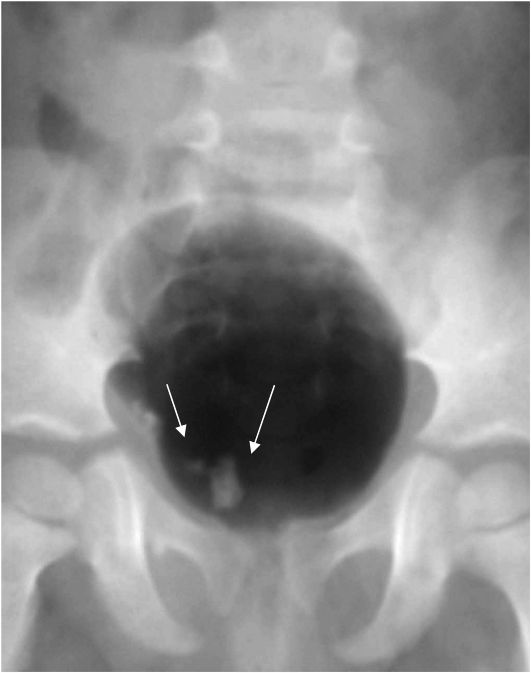

Изображения КТ конкрементов мочевого пузыря